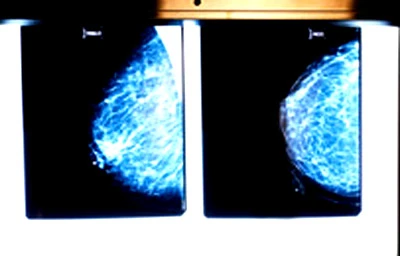

5. Quang tuyến - Kỹ thuật phát hiện ung thư vú cho tuổi 50

Đây được coi là một vụ xcan-đan

Đương nhiên, không có phương pháp xét nghiệm nào được xem là hoàn hảo, tức là trong số 100 phụ nữ có kết quả quang tuyến dương tính thì có đến 23 người không bị ung thư vú, nhưng trong số 100 người có kết quả âm tính thì có 6 người thật sự mắc bệnh ung thư vú. Do đó, kết quả dương tính giả và âm tính giả là một trong những khiếm khuyết của xét nghiệm ung thư vú bằng quang tuyến.